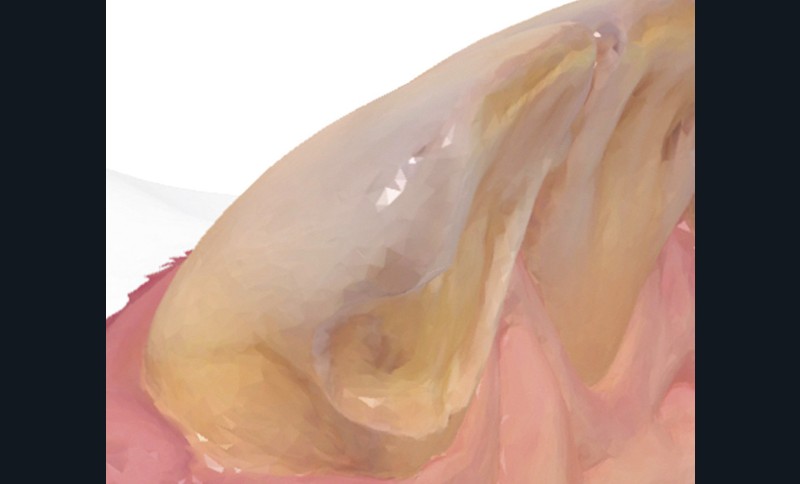

Une fois les modèles virtuels créés, l’armature du bridge est modélisée par Conception Assistée par Ordinateur sur le logiciel Trios Design Studio (3Shape) (fig. 10). La surface de connexion mesurée est de 9,8 mm2 (fig. 11) et celle de collage de 40,56 mm2, respectant ainsi les recommandations de la littérature [24].

L’armature est usinée (Zenotec Select, Wieland dental) dans un disque de zircone (Zenostar Zr Translucent, Wieland Dental) (fig. 12) puis sintérisée (Tabeo, Mihm-Vogt) (fig. 13). Les modèles numériques sont conjointement imprimés en 3D (Mars Pro, Elegoo) afin d’obtenir un modèle physique nécessaire à la stratification de la céramique cosmétique (Emax Ceram, Ivoclar Vivadent) (fig. 14a-b).